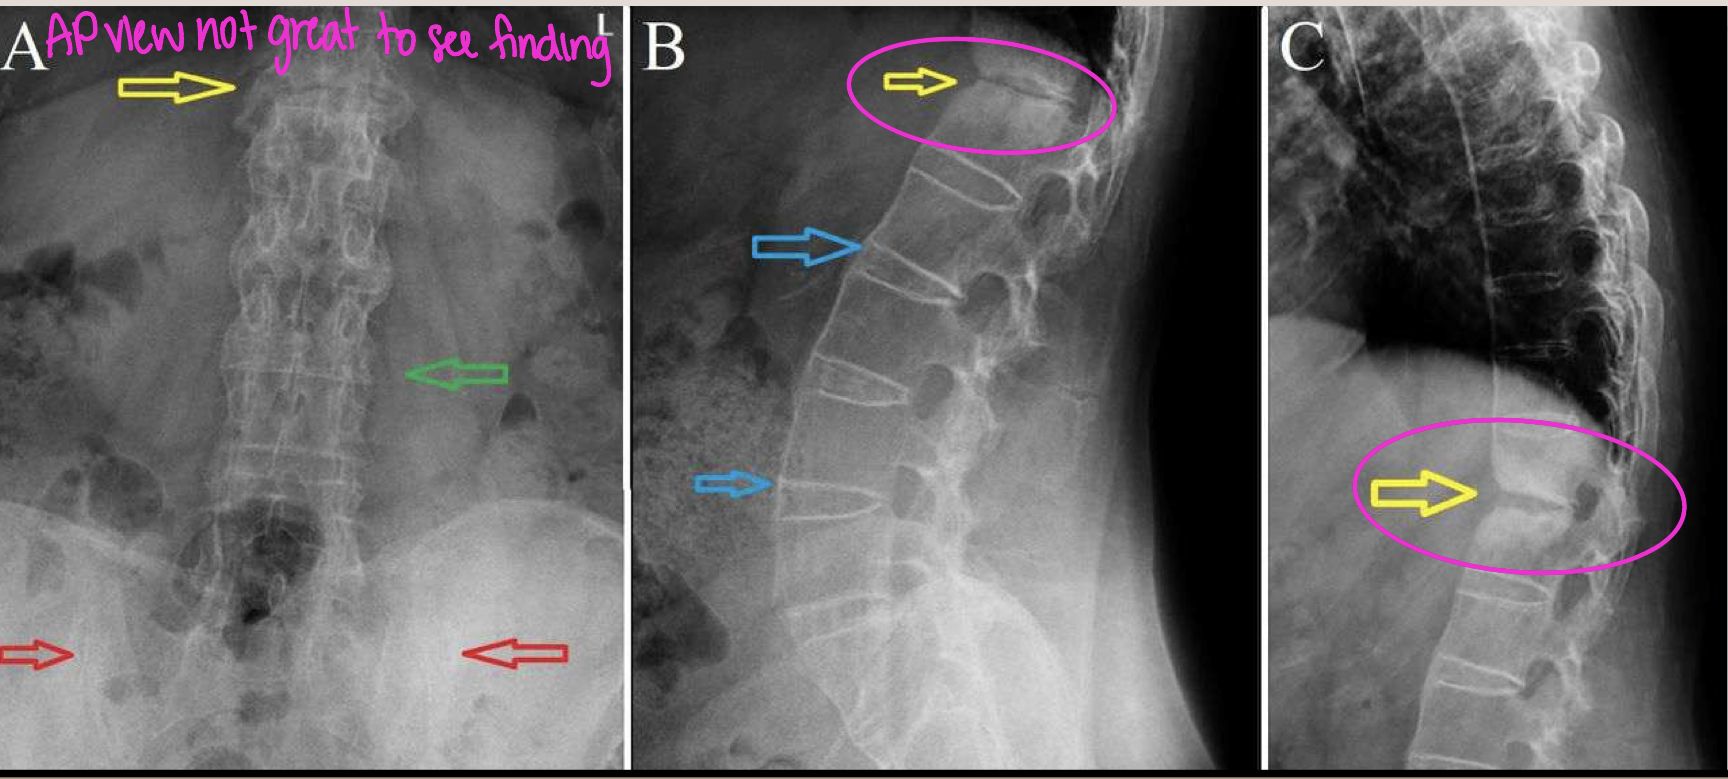

What finding of AS is found in this image

Endplate destruction (Andersson lesion)

causes loss of mobility and ability to shock absorb

Andersson lesion is also known as

rheumatic spondylodiscitis

Spinal fracture (Carrot/Chalk stick fracture)

IVDs hold vertebrae together still but can’t withhold forces